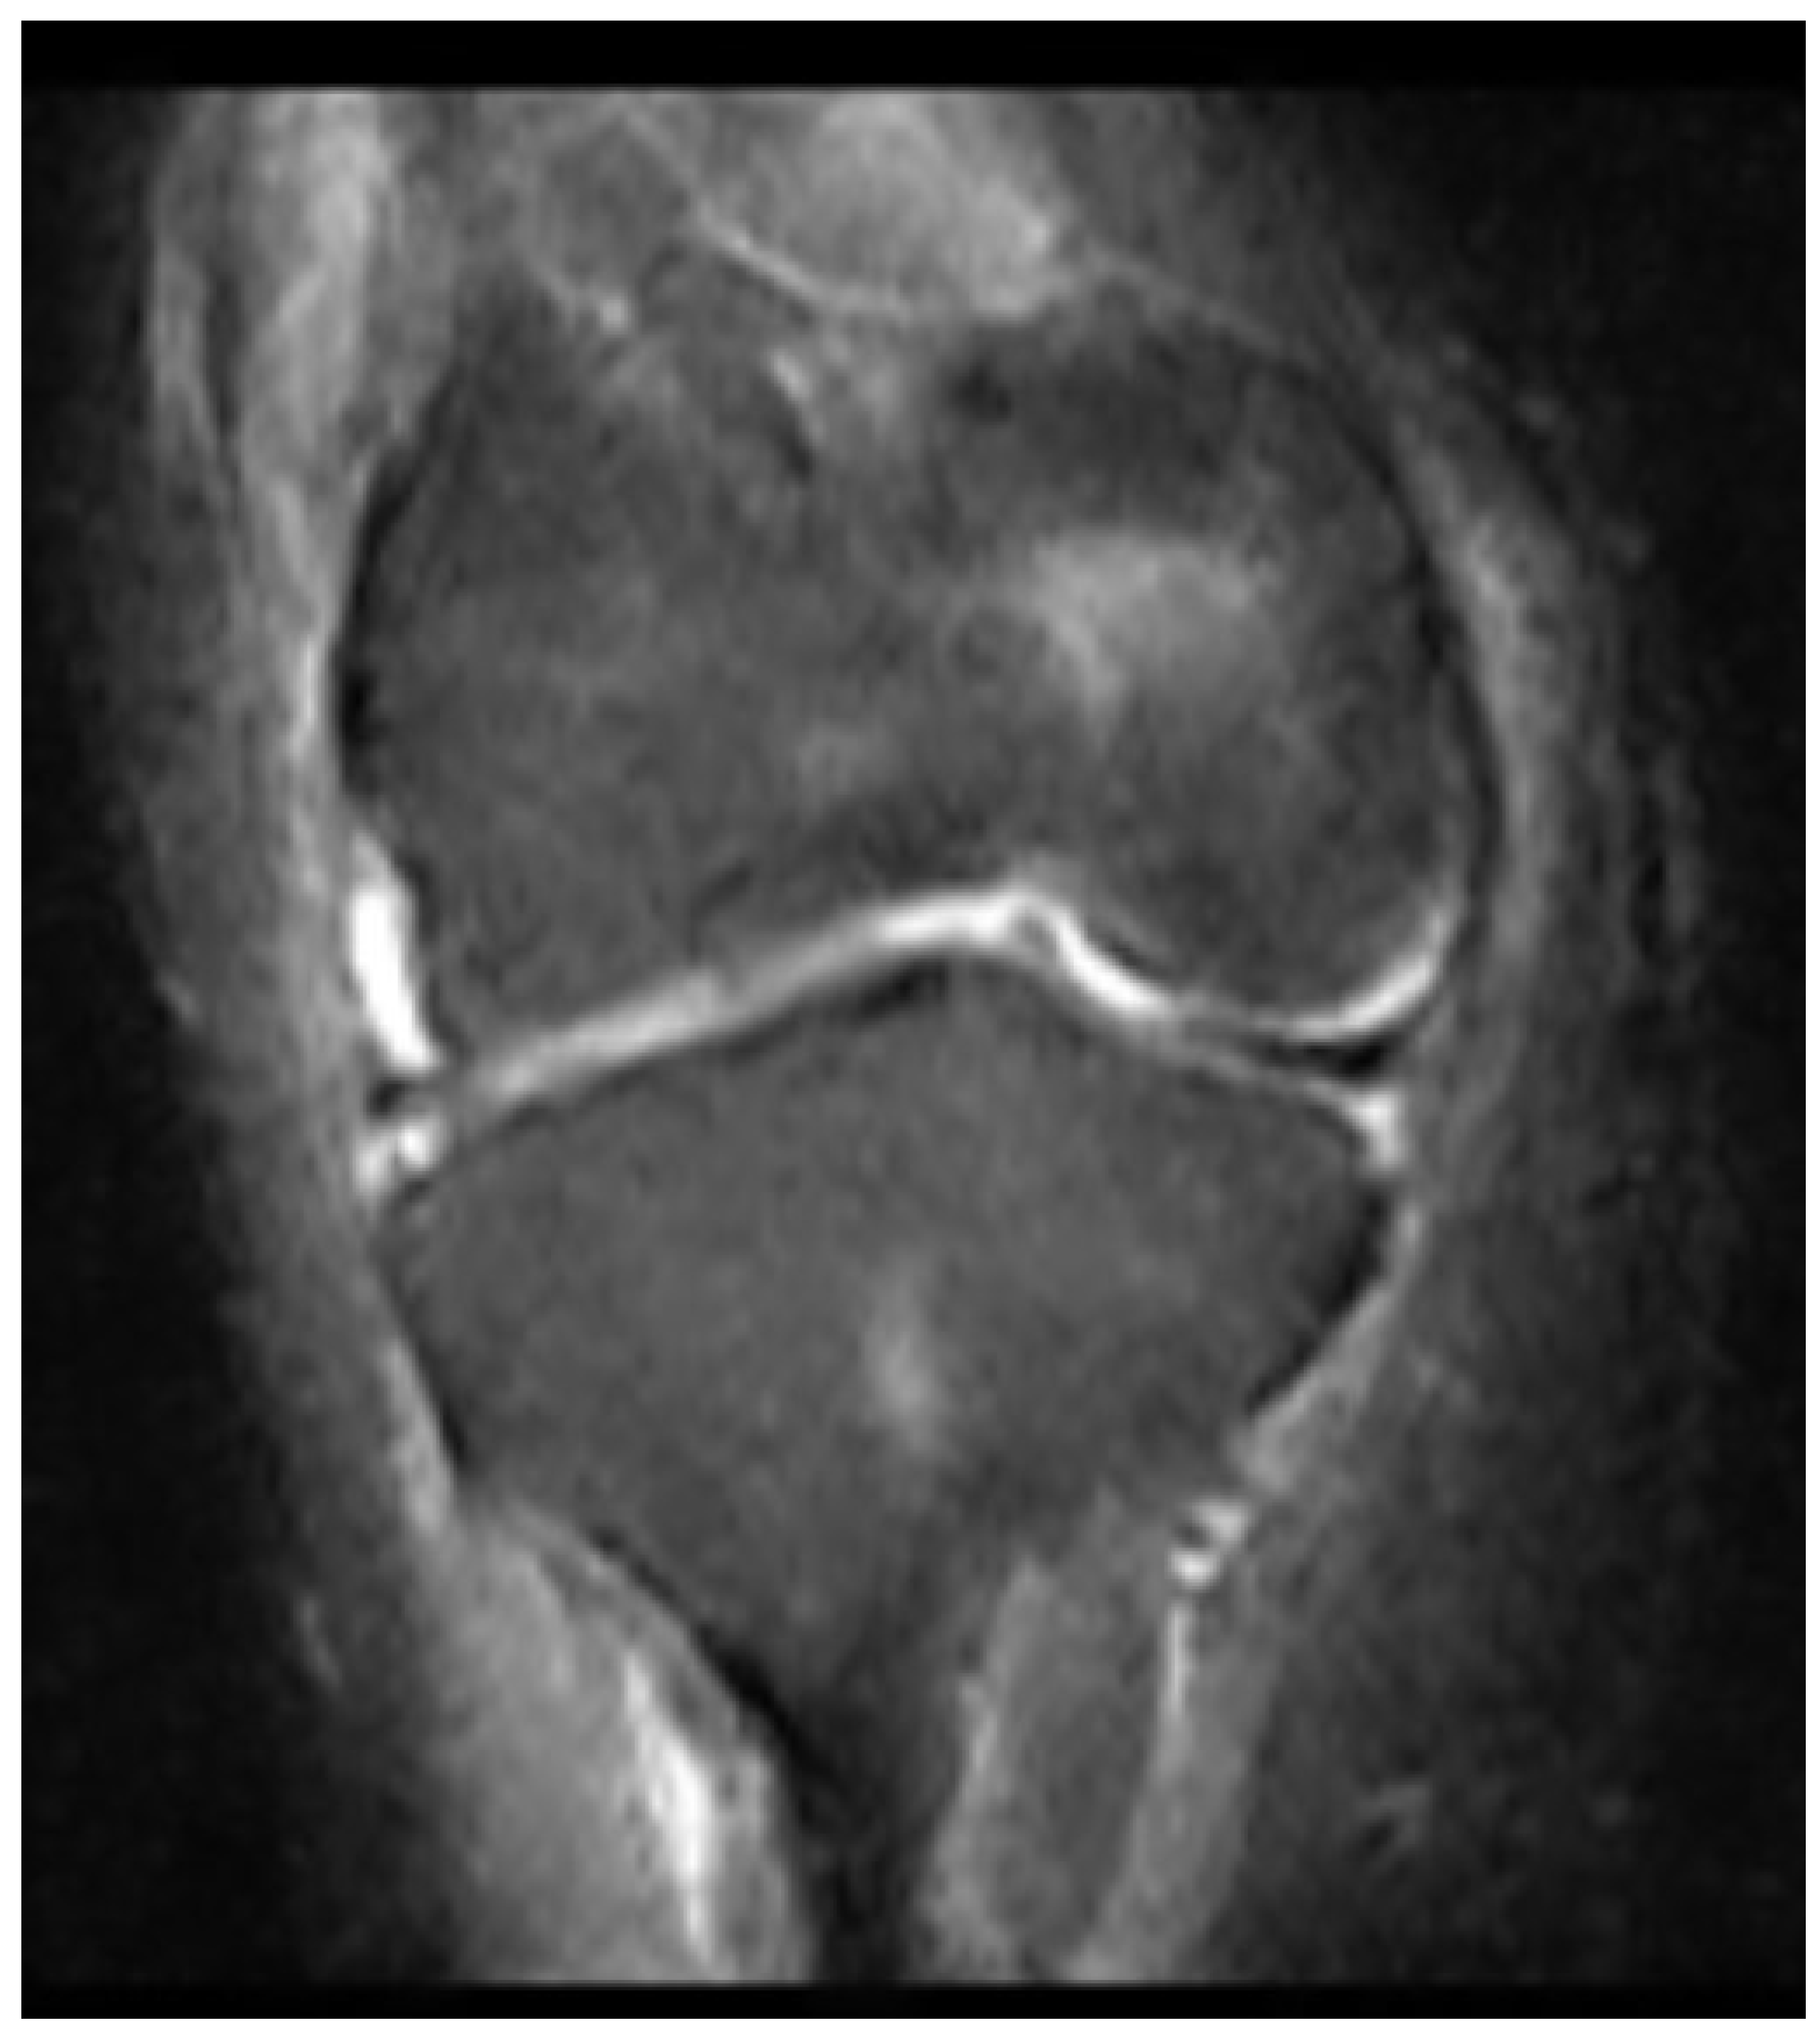

2 years later, at the age of 16, the tibial intramedullary nail was removed and finally, magnetic resonance imaging (MRI) of the knee was acquired. This showed complete agenesis of both the anterior and posterior cruciate ligaments (Figure 9) (Figure 10).

Figure 9. caption.